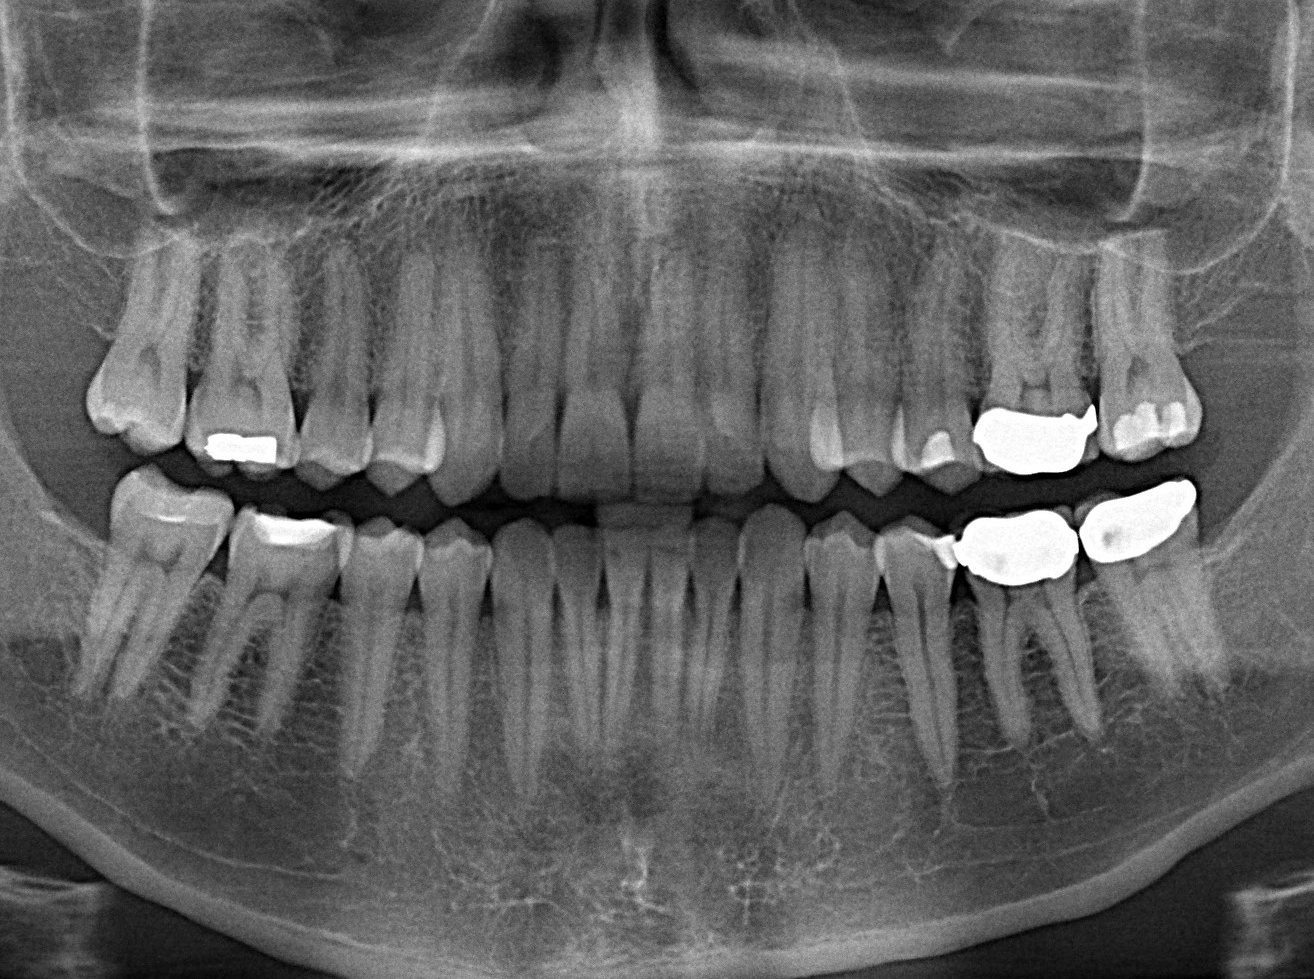

Visited the dentist today. Here was my x-ray. This was the first time I used this machine that I put my head into and it rotated around my head.